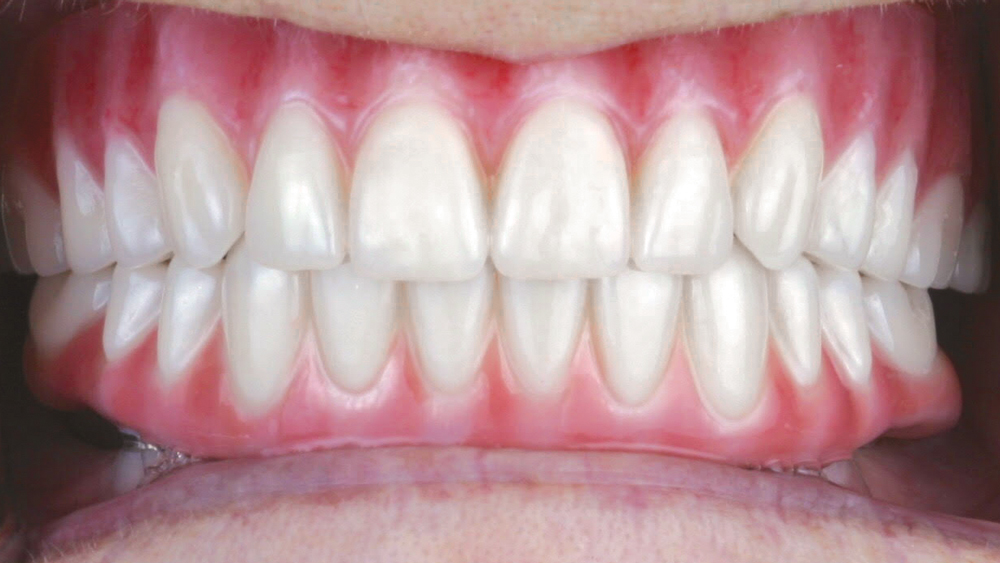

This patient was unhappy with the esthetics of her existing upper denture as well as the discomfort and instability caused by her loose-fitting mandibular partial denture. Although her concerns with the maxillary denture could be addressed with a new, more esthetic appliance, she preferred implant treatment for her mandible, where a fixed solution was needed to adequately restore function, stability and comfort.

The patient’s remaining mandibular teeth were extracted followed by immediate implant placement and delivery of a fixed provisional appliance. After integration of the implants, the prosthetic designs for the new upper denture and lower implant restoration were determined in tandem. Ultimately, the dual-arch restorations addressed the functional and esthetic challenges of the case while staying within the financial means of the patient, demonstrating the benefits of a flexible, multifaceted approach to restorative dentistry.

The dual-arch restorations addressed the functional and esthetic challenges of the case while staying within the financial means of the patient.